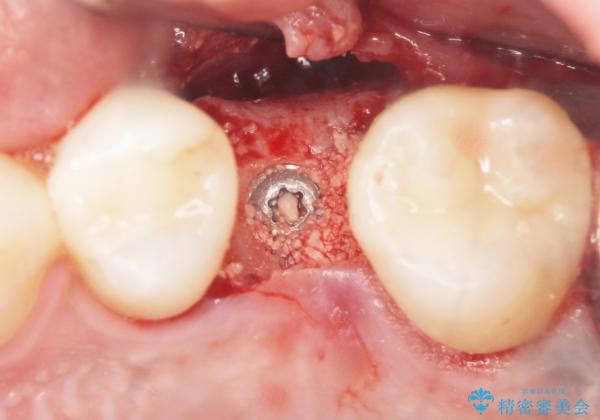

残根状態になっている左上の小臼歯(左上5)を精査したところ、う蝕が歯肉縁下まで進行しており保存不可能な状態でした。

患者様のご希望により、抜歯後インプラント治療を行いました。

骨の厚みが不足していたため、インプラントの埋入と同時にソケットリフト(上顎骨に骨を増やす手術)を行いました。